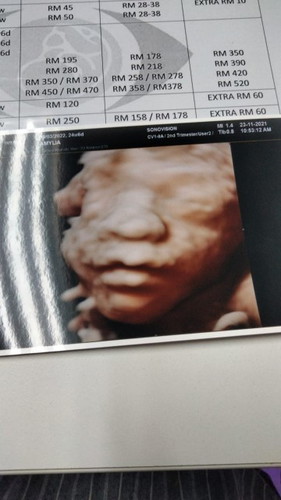

Alhamdulillah done buat 5D ultrasound scan at sonovision ultrasound scan centre kelana jaya harini and already confirmed the baby gender its a baby boy!!! Syukur sgt dgn rahmat Allah SWT bagi ni, im a happy mother! #firstbaby #6monthsofmypregnancy #25_weeks #1stimemom